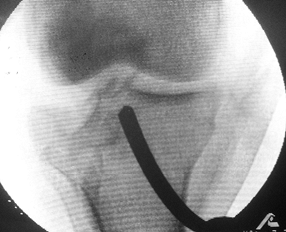

tomography for the evaluation of displaced tibial plateau fractures. CT

scanning with sagittal reconstruction has increased the diagnostic

accuracy in tibial plateau fractures and is indicated in cases of

articular depression (Fig. 23.5) (19,43).

![]() |

|

Figure 23.5. A CT scan is shown with two-dimensional reconstructions demonstrating a pure depression fracture.